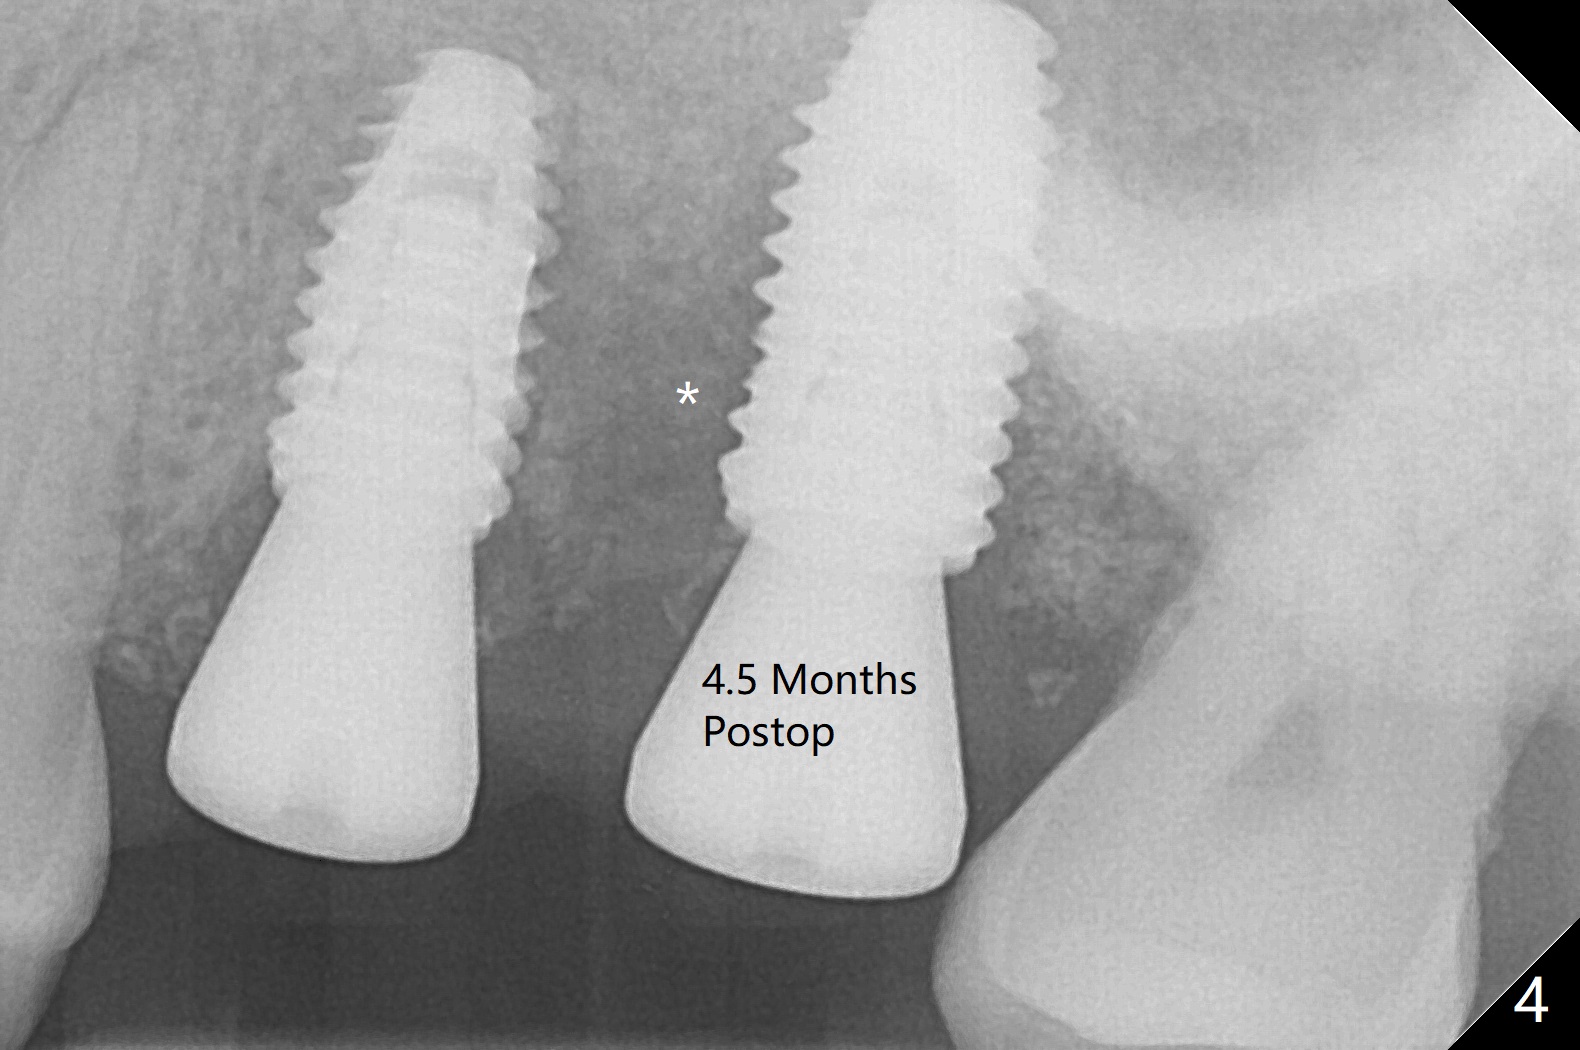

Fixture mount does not fit at #13 as an anchor. After 3.5x7.3 mm drill with 10.5 mm offset at #14, sinus lift drills (3.6x18 and 19 mm) are used. The sinus floor is intact. A 9 mm offset should be used. Following 4.0x10 mm dummy implant is placed for ~ 8.5 mm, the sinus floor is perforated while the sinus membrane is intact. After water lift, PRF membrane and allograft are inserted and pushed upward with the 4.0x10 mm dummy implant for ~ 10 mm (Fig.1). One more piece of PRF membrane and bone graft are lifted with a 4.5x10 mm dummy implant. A small dose of bone graft is elevated with a definitive implant (Fig.2,3, 5x10 mm). Is there enough bone to cover the apical part of the implant when the latter heals? When the patient returns for restoration 4.5 months postop, local oral hygiene is not good with light gingival erythema. There is tenderness when the healing abutment is being removed. It appears that osteointegraton is to occur; the mesial bone density is low (Fig.4 *). Healing abutment should be not placed when sinus lift repeatedly fails. In fact the implant is removed with the healing abutment 6.5 months postop. The buccal plate is missing, while the sinus floor is intact. Ossogen is placed, covered by Osteogen plug and sutured with PGA (Fig.5). The buccal plate remains concave 8 days postop (Fig.6 B). In the 4th trial, incision will be made, flaps dissected extensively with suture fixation. The existing guide is used to start osteotomy with point drill, followed by bone expansion. Reload the guide to place a narrower implant 4 or 4.5 mm with cover screw, and place sticky bone buccal. The latter is covered with PRF and suture. If stability is insufficient, perforate the sinus floor. Place a cemented abutment at #13 to hold periodontal dressing. Use profile drill if needed.Return to Upper Molar Immediate Implant, Trajectory II Xin Wei, DDS, PhD, MS 1st edition 08/13/2019, last revision 02/13/2021